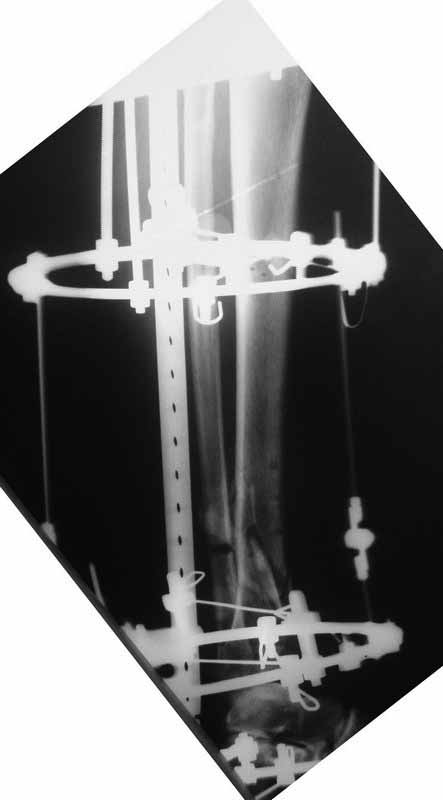

Боюсь, кусок гвоздя в канале будет сильно мешать, так что мы бы открыли бы над ним передне-медиальную кожно-надкостнично-костную "крышку", и убрали. То есть не скелетировать чтобы кость даже вдали от несращения.

А так - согласен с Алексеем, аппаратная репозиция (если тугоподвижность - то за несколько дней), зону несращения не открывать, рассверлить, помыть, стержень с антибактериальным цементным покрытием.

Если свищи - может, действительно спейсер на насколько недель сначала.

Подвинуть новый гвоздь обломок сможет, а вот блокировать может не дать. Мы и отломок гвоздя попробовали бы удалить закрыто.